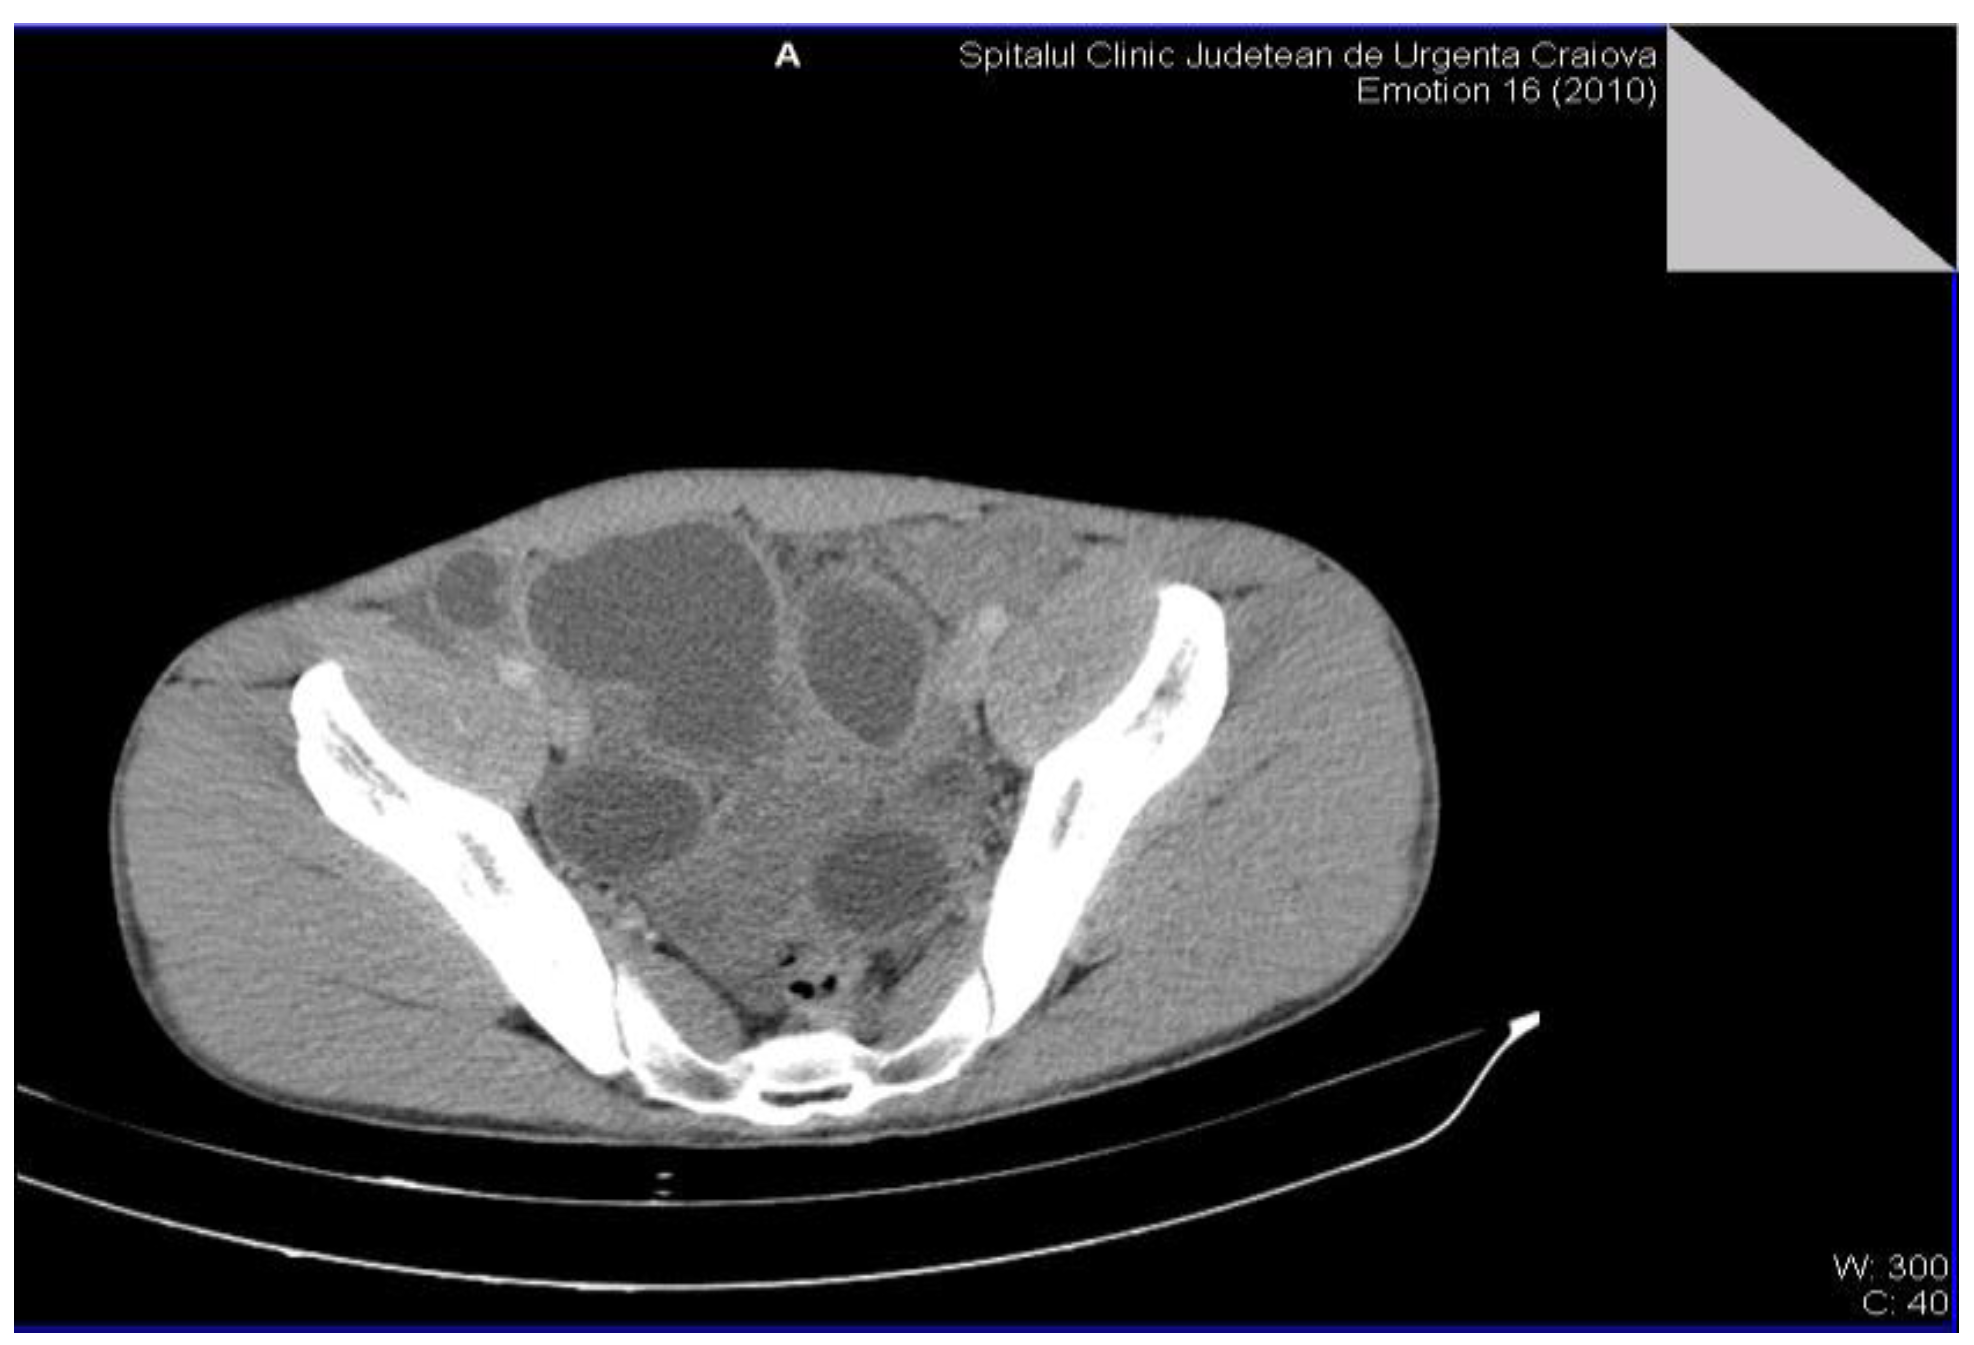

The definitive diagnosis of the retroperitoneal hydatid cyst was based on the anamnesis, clinical examination and paraclinical examinations, including serological examinations. The medical history of the patients was insignificant, but most of them were from rural areas and confirmed the close interaction with animals (sheep, goats, dogs). The clinical examination very rarely raises the suspicion of retroperitoneal hydatid cyst, the examinations of other systems and organs being normal. Most of the biological investigations were within normal limits. The serological examination by detecting the immunoglobulin G antibody by the ELISA method (enzyme-linked immunosorbent assay) was positive in all cases, showing high sensitivity and specificity and was only performed after raising the suspicion of hydatid cyst by imaging methods. Non-invasive imaging paraclinical investigations for the diagnosis of the disease were: abdominal (or regional) ultrasound, CT scan (computed tomography) and MRI (magnetic resonance imaging) that proved a high sensitivity. The presence of daughter cysts, hydatid sands, and floating membrane can confirm the diagnosis of hydatid cyst [6,7]. Abdominal ultrasound established the diagnosis in the case of 4 patients, and in the case of two patients it raised the suspicion of retroperitoneal hydatid cyst. The CT examination was carried out in 5 patients, for diagnostic purposes or for the remote evaluation of the lesions. In 2 patients, the tomographic diagnosis was accidental, without clinical or paraclinical suspicion of abdominal hydatid cysts and revealed their single or multiple presence, either only retroperitoneally or also intraperitoneally (Figure 2 and Figure 3).

Figure 2.

Multiple intra-abdominal hydatid cysts.

Figure 3.

Intra-abdominal hydatid cysts.